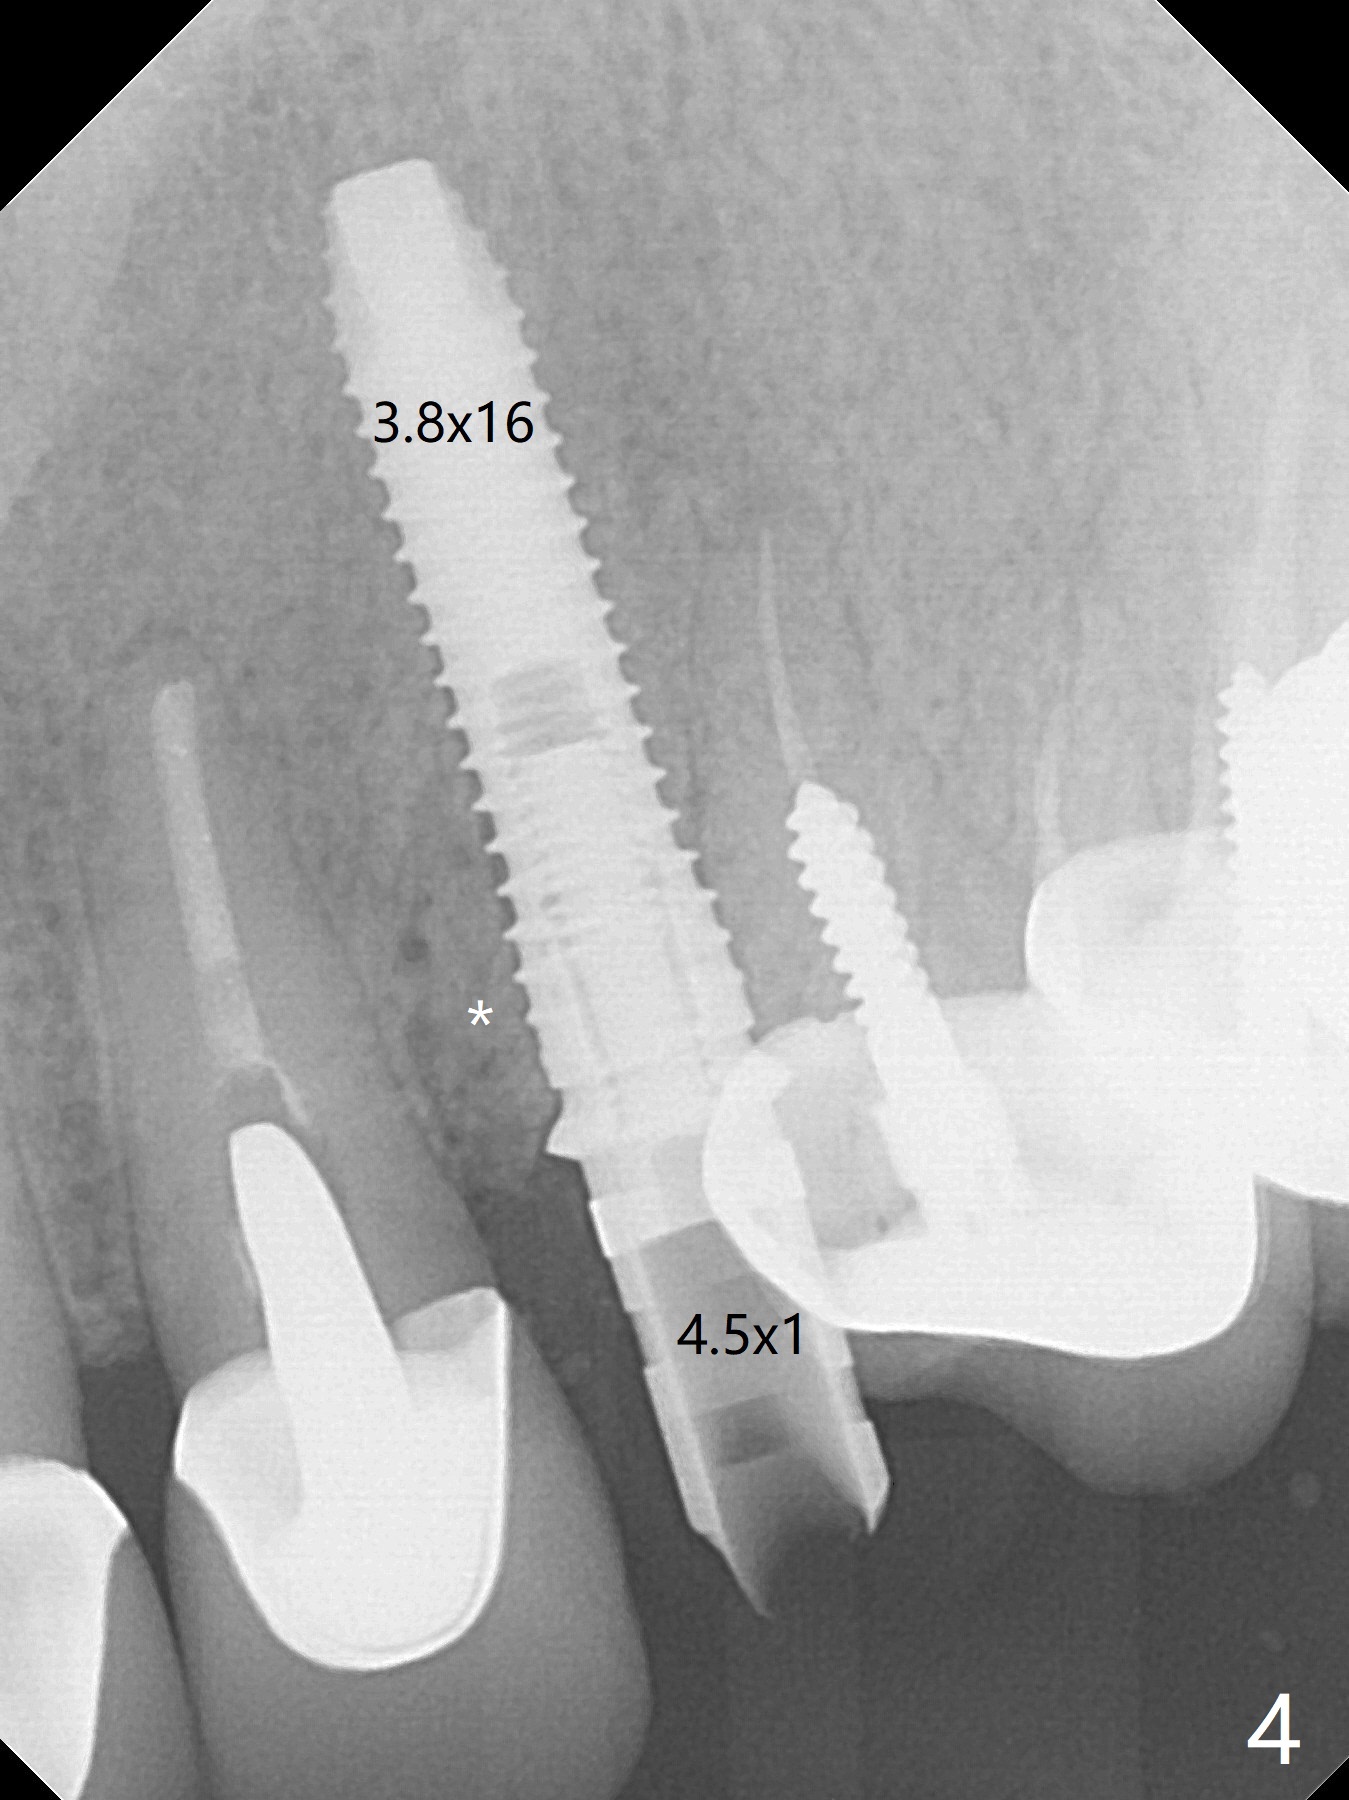

In spite of severe apical infection (Fig1,2 *), a thin narrow strip of the buccal plate (arrowheads, corresponding to the keratinized gingiva) is present when the tooth #11 is extracted. The thin bone keeps the bulging alveolus, i.e., reservoir for bone graft (Vanilla/Osteogen Fig.4 *) after placement of a 3.8x16 mm implant (Fig.3,4). A 4.5x1 mm temporary abutment, placed and trimmed for an immediate provisional, seems to be short in cuff. When an implant is placed deep to prevent periimplantitis, the cuff should be longer, i.e., 3 mm. X-ray should be taken for the depth confirmation after temporary abutment placement. Eight days postop, the mesial gingiva erythema has subsided (Fig.5 < (P: provisional)), while the apical swelling is no longer tender and most likely due to packed bone graft (*). Panoramic X-ray taken 2 weeks postop shows the clearance from the nasal cavity or the maxillary sinus (Fig.6). While the hard tissue around the implant seems to be healthy 5 months postop (Fig.7), the soft tissue is not (Fig.8). The temporary abutment is changed to a cemented one (4.5x5(2) mm) for impression (Fig.8). Since the neighboring crowns are PFM (Fig.6), the new crown will be made of the same material for shade match. Indeed PFM helps shade match in this case as well (Fig.9,10). Switching abutments (from temporary to cemented) makes it difficult to seat the crown. Post cementation X-ray leaves record for future contact loosening. The buccal gingiva remains erythematous associated with open margin (Fig.11 >) 1 year 4 months post cementation. There is no obvious bone loss 1 year 4 months post cementation (Fig.12). It appears that the crown and abutment need to be changed. Although the gingival margin remains erythematous, the gingival hemorrhage is basically lacking due to better oral hygiene during Shelter at Home (1 year 9 months post cementation, Fig.13). Change in abutment and crown will be conducted post coronavirus pandemic. In fact the abutment is incompletely seated (Fig.14 <). In addition, the tooth #12 is symptomatic with PARL associated with the buccal root (*). CBCT indicates possible buccal root fracture (Fig.15,16 ^) and loss of the buccal plate (Fig.16 <).